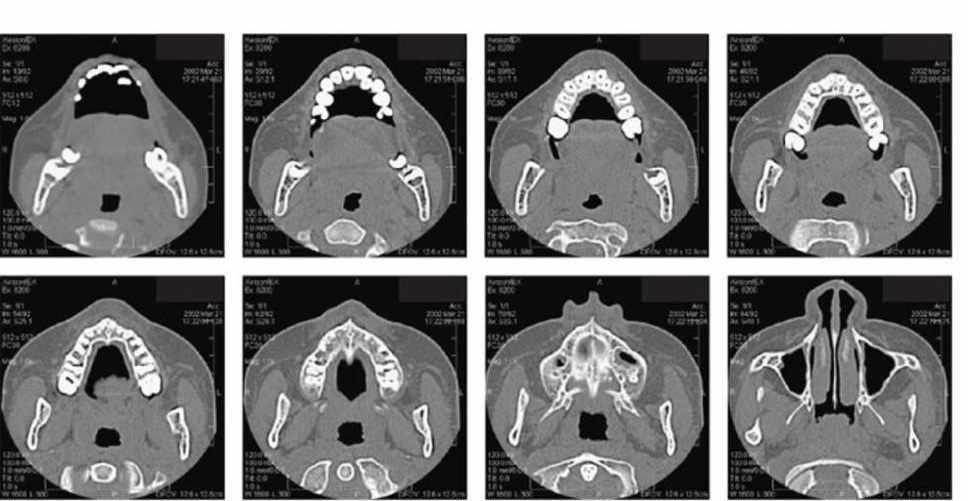

Geralmente o exame da região dos maxilares é compostos por 4 tipos de reconstruções: axiais, coronais, sagitais (ou parasagitais) e ortorradiais. Esta parece ser uma boa seqüência para a interpretação das imagens. A figura 18B mostra os cortes axiais, numa seqüência arco dentário-cavidade nasal. A primeira imagem mostra, no lado.

Caninos, primeiros e segundos pré-molares, primeiros e segundos molares foram examinados em cortes axiais, coronais e sagitais. As raízes vestibulares desses dentes foram avaliadas da face mesial até a distal. Resultados: Todas as análises estatísticas foram realizadas usando os softwares SAS 9.3 e SUDAAN. O alfa usado no estudo foi de 0,05.

Na tela de reconstrução multiplanar, os cortes axiais, coronais e sagitais foram realizados no longo eixo de cada dente. A partir dos cortes sagitais, para os caninos e incisivos laterais e dos cortes coronais, para os primeiros pré-molares, foram mensurados comprimento radicular e os níveis de inserção óssea vestibular e palatina.